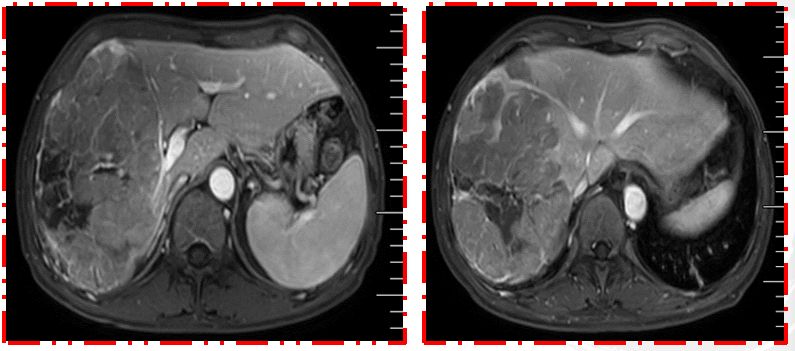

患者男性,68岁,既往乙肝病史20余年。发现肝占位10天就诊。就诊时AFP>1200↑ng/mL, DCP 20000↑ng/mL,CEA 13.48↑ng/mL;影像MRI:肝右叶异常信号并肝右静脉、门静脉右支受侵,符合肝Ca MR表现(影像如图1所示)。

首诊影像MRI